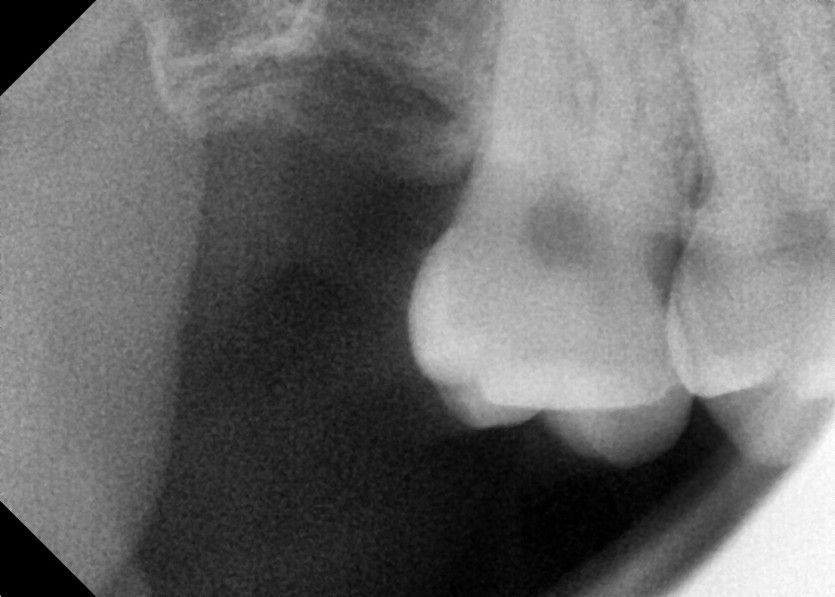

#18,48 사랑니 발치

구강 외과 전문의가 당일 발치했습니다.